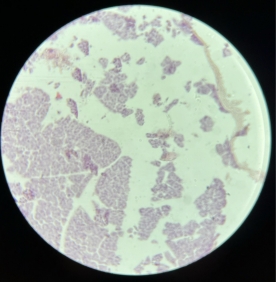

Mucous Tissue